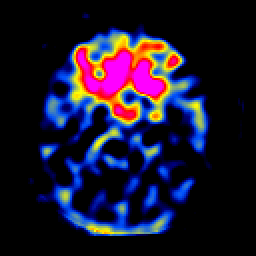

SPECT TL Study #6 -- Slice #19